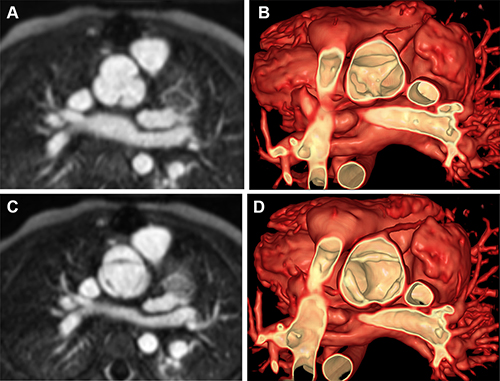

Figure 3. Volume rendering of ferumoxytol-enhanced cardiac MR images using image-based navigation (ie, iNav) to inform closure of multiple ventricular septal defects (VSDs) in a 3-year-old female patient (patient 3). (A) Multiplane reconstruction of volume demonstrates muscular VSD (green arrow). (B) Volume rendering of the myocardium from right ventricular view. (C) Volume rendering of the myocardium from left ventricular view. (D) Simulated VSD closure (blue) and device placement (green) within volume-rendered images.